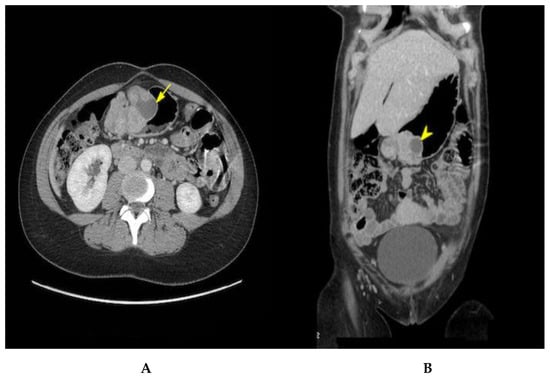

The patient was induced at 37 + 1 week. The baby was born with no immediate complications with an Apgar score of 9-9-10. She was discharged 2 days postpartum and was readmitted again a week later for her elective surgery. A preoperative abdominal CT with contrast was performed (Figure 1). The mass seemed to have progressed, now measuring 8.3 cm. A 10 mm enhancing retroperitoneal lymph node anterior to the aortic bifurcation suspicious for metastasis was noted. A 10 mm enhancing retroperitoneal lymph node anterior to the aortic bifurcation was visualized, with a suspicion of metastasis. Partial gastrectomy and a Billroth type I reconstruction were performed. During surgery, macroscopic lymph nodes were detected across the gastro-epiploic artery. Consequently, a lymphadenectomy extending to the hepatic pedicle was completed.

Figure 1. Axial (A) and coronal (B) contrast-enhanced CT view showing an 8.3 cm polylobate submucosal lesion with cystic components (yellow arrows) consistent with a GIST.